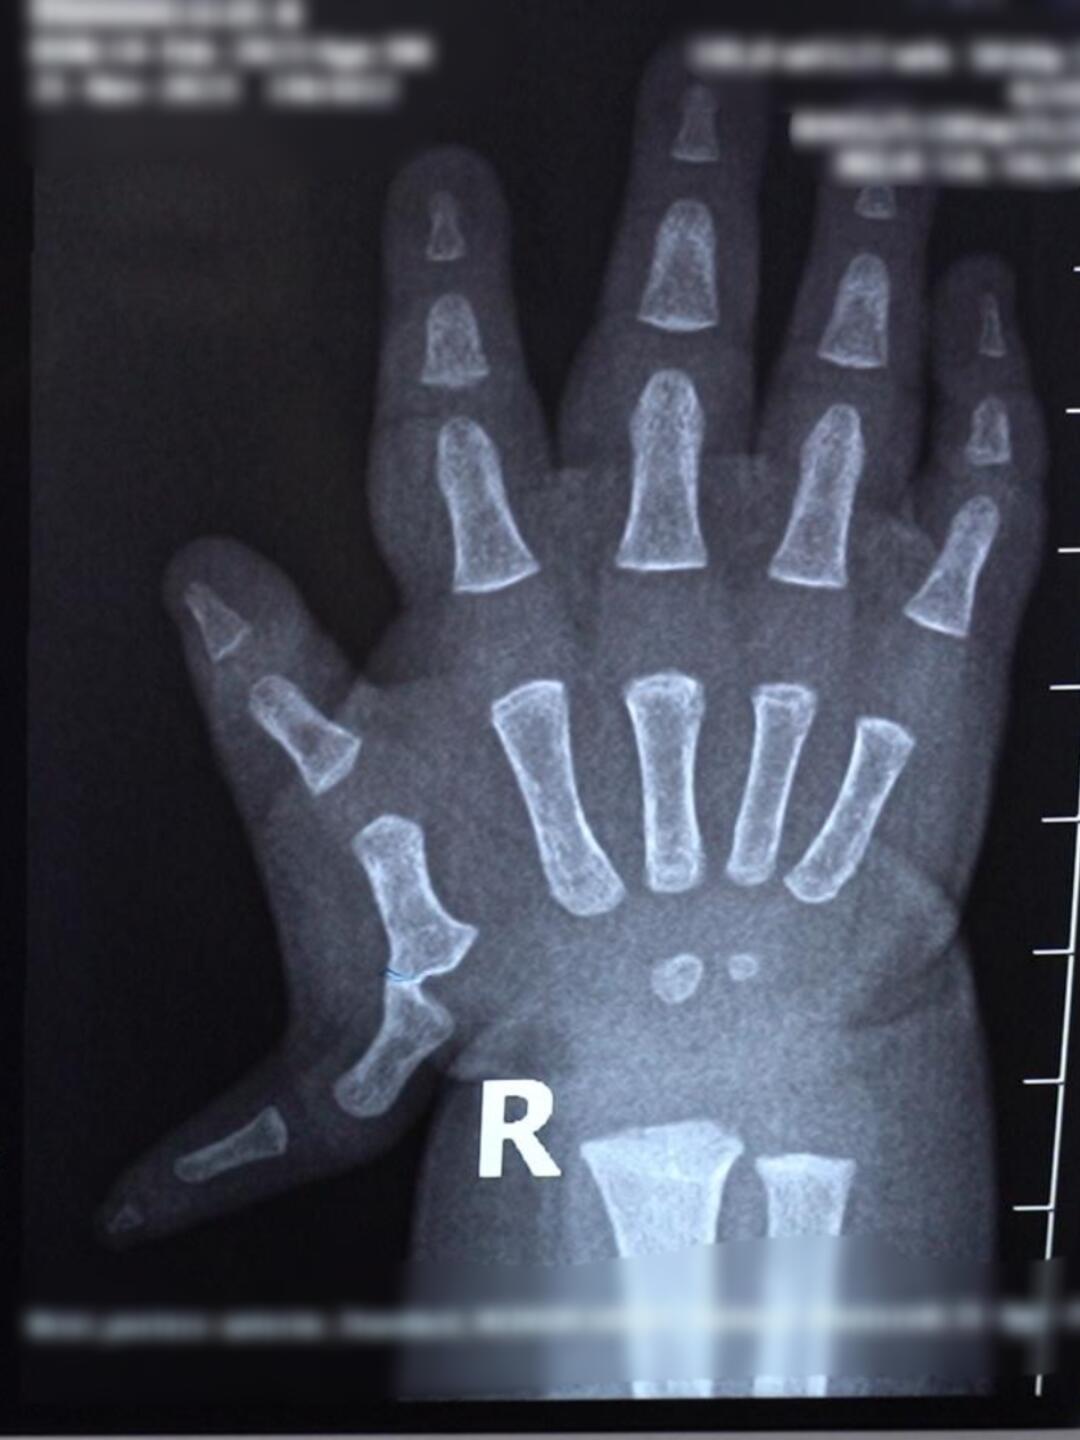

成年人多指

图片尺寸960x720

成年人多指案例